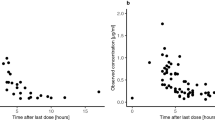

Individual pharmacokinetic parameters were determined for each patient using a previously developed two-compartment model for bevacizumab [23]. The model predicted Cmin and Cmax concentrations reasonably well (Fig. 3; individual profiles: Fig. S2, Online Resource) and was used to describe the serum concentration–time profiles of the patients also at later time points (Fig. 4).

Measured serum concentrations (blue circles) and predicted serum concentration–time profiles of bevacizumab (BVZ) based on a previously published population pharmacokinetic model for pediatric cancer patients [23]

To quantify bevacizumab penetration into CSF, an additional compartment was added to the model (Fig. 1). The difference between serum and CSF concentrations was modelled using an uptake factor (UPTK), which was 0.16 for the typical patient in the population. The model significantly improved when allowing interindividual variability on the uptake factor (ΔOFV 48.5) and revealed a broad range of individual estimates between 0.02 and 0.66 (median 0.17). Simulations considering between-patient variability in the pharmacokinetic parameters revealed a median ratio of AUCPL/AUCCSF of 0.156 (95% prediction interval 0.00282–0.897).

Goodness-of-fit plots indicated good agreement between the observed and predicted data (Fig. 5), without any striking trends and with random scatter around the line of identity or reference line (conditional weighted residuals: Fig. S3, Online Resource). Individual predicted profiles (Fig. S4, Online Resource) were reasonably predicted given the sparse data situation, and the visual predictive check showed acceptable predictive performance of the model, with slight overestimation of interindividual variability (Fig. 6).

Visual predictive check of the model for cerebrospinal fluid concentrations of bevacizumab (BVZ). Blue circles represent measured BVZ concentrations; the blue solid line shows median observed concentrations, and the blue dashed lines indicate the 10th and 90th percentiles of the observed data. The green solid line shows the median of model predictions. Shaded areas depict the 95% confidence intervals for the prediction lines (median, 10th and 90th percentile)